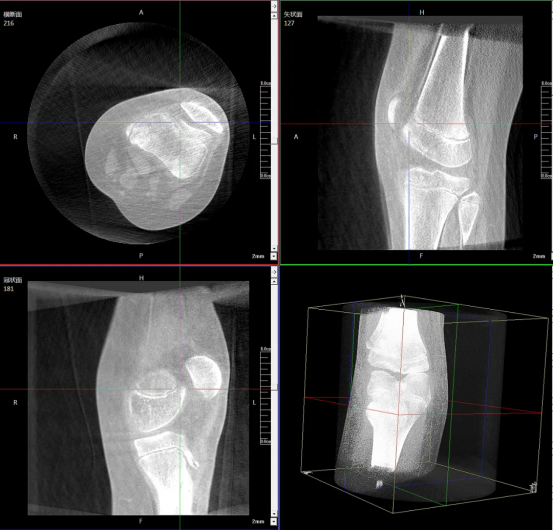

Preoperative Imaging

Intraoperative 3D images were acquired by the Perlove Medical’s 3D C-arm.